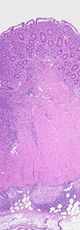

داء كرون Crohn's disease سمي بهذا الاسم نسبة للدكتور بوريل كرون والذي هو أول من وصف الداء عام 1932 في نيويورك. يمكن تعريف داء كرون بأنه أحد الأمراض الالتهابية المزمنة المجهولة السبب يصيب الجهاز الهضمي بشكل عام مع إمكانية ترافقه مع بعض الإصابات الجلدية أو المفصلية.

يصيب داء كرون جزء من الجهاز الهضمي قد يبقى مقتصراً على هذا الجزء أو يصيب أجزاء أخرى في كل هجمة . إن المنطقة الأشيع للإصابة هي نهاية الأمعاء الدقيقة وبداية الكولون ( الأمعاء الغليظة ) حيث تصاب بالإلتهاب والتقرح. في هذه الحالة يشكو المصاب من ألم بطني ( خاصة في الربع الأيمن السفلي من البطن ) وارتفاع معتدل في درجة الحرارة ونقص في الشهية ( قهم ) وهبوط في الوزن قد تترافق هذه الأعراض بحدوث الإقياء والإسهال . تشبه هذه الأعراض أعراض التهاب الزائدة الدودية مما قد يقود إلى استئصالها خطأ قبل تشخيص المرض.

غالباً مايعاني المريض لفترة طويلة قبل تشخيص الإصابة بداء كرون . حيث تشترك أعراضه مع أعراض العديد من الأمراض الأخرى ولكن تكرر هذه الأعراض وشدتها توحي بشكل قوي بالتشخيص , إلا أن التشخيص الأكيد لايتم بسهولة . يساعد على وضع التشخيص مجموعة من تحاليل الدم والتصوير بالأمواج فوق الصوتية والتصوير بالطبقي المحوري المحوسب وتصوير الأمعاء الدقيقة الظليل والتصوير باستخدام الكبسولة المعوية والتنظير الهضمي ( العلوي والسفلي ) والذي يعتبر الأهم من ناحية التشخيص لأنه يتيح لنا الرؤية العيانية والحصول على عينة للفحص النسيجي.